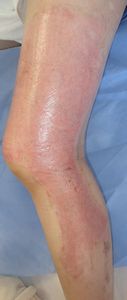

2016年2月19日,母から手渡された湯たんぽ(ゴム製)が破裂し,両手,両下肢に熱傷受傷。〇〇大学附属病院に救急搬送されて処置を受けたが,ベッドの空きがないため,△△病院に転送され形成外科に入院となった。ゲンタシン軟膏とフィブラスト,シリコンガーゼでの治療を受けたが,毎日処置をする医師が変わり,治療に対する説明は全く無く,おまけに処置の際に乱暴にガーゼを剥がされ,そのたびに激痛で,毎日の処置が憂鬱だった。3月2日に退院し,通院するように説明されたがもう治療を受けたくないため,ネットで熱傷治療について検索。

3月10日,当科受診。痛みで歩けず,車いすで診察室に入ってきた。右大腿のガーゼは除去できたが,左大腿〜下腿のガーゼが固着し,ガーゼが除去できなかった。そのため,ガーゼの上からたっぷりワセリンを塗布し,その上は穴あきポリ袋で被覆し,吸収シートで覆い,その状態で帰宅してもらった。

翌日,車椅子でなく歩いて診察室に。「帰宅してしばらくしたら痛みがなくなり,普通に歩けるようになりました」とニコニコ。ガーゼも痛みなく除去できた。以後は両足ともに「穴あきポリ袋+吸収シート」で治療。

| 右大腿内側 | 左下腿前面:ガーゼ固着 | 穴あきポリ袋で被覆 |